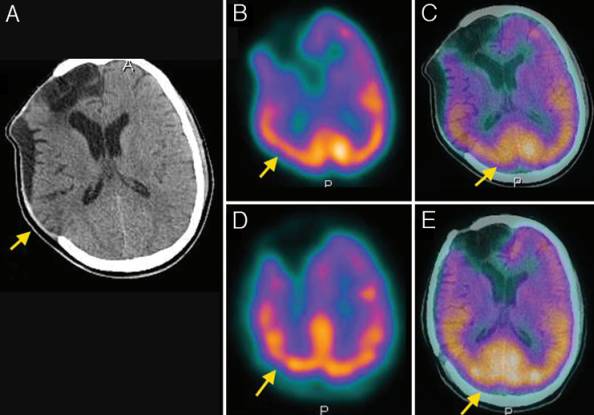

结果显示,颅骨成形术前,9例(26.5%)患者的GOS评分为5分,25例(73.5%)GOS评分为4分;颅骨成形术后,34例(100%)患者GOS评分为5分,较术前提高。各项认知测试结果表明,35.3%-90.9%的患者于颅骨成形术后认知功能改善(表1)。此外,94%患者的脑SPECT成像结果提示,在不同脑叶中脑灌注情况均得到改善(图1-4)。

图1. A.颅脑CT显示右侧颅骨缺损;B、C.颅脑SPECT示术前额叶、顶叶、枕叶的脑血流灌注降低;D、E.颅脑SPECT示术后脑血流灌注较术前改善。